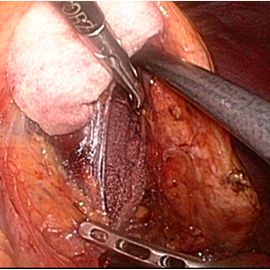

手術画像